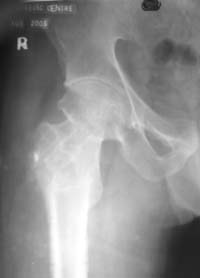

Dynamic hip screw with abduction osteotomy with an additional cancellous screw